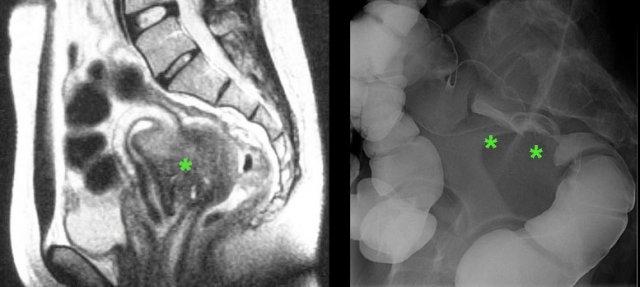

Trong các trường hợp DIE nặng và kéo dài, khối mô sẹo lớn của DIE (*) có thể gây hẹp và cuối cùng là tắc nghẽn hoàn toàn lòng đại tràng.

Ở bệnh nhân nữ trẻ này với các triệu chứng đau bụng mạn tính không rõ nguyên nhân kéo dài nhiều năm, CT và MRI tiếp theo đã phát hiện lạc nội mạc tử cung lan rộng.

Ngoài ra, còn ghi nhận các nang lạc nội mạc tử cung lớn có dính (“buồng trứng hôn nhau”), ứ nước thận hai bên và tắc nghẽn hoàn toàn đại tràng do lạc nội mạc tử cung xâm lấn vào niệu quản và trực tràng.